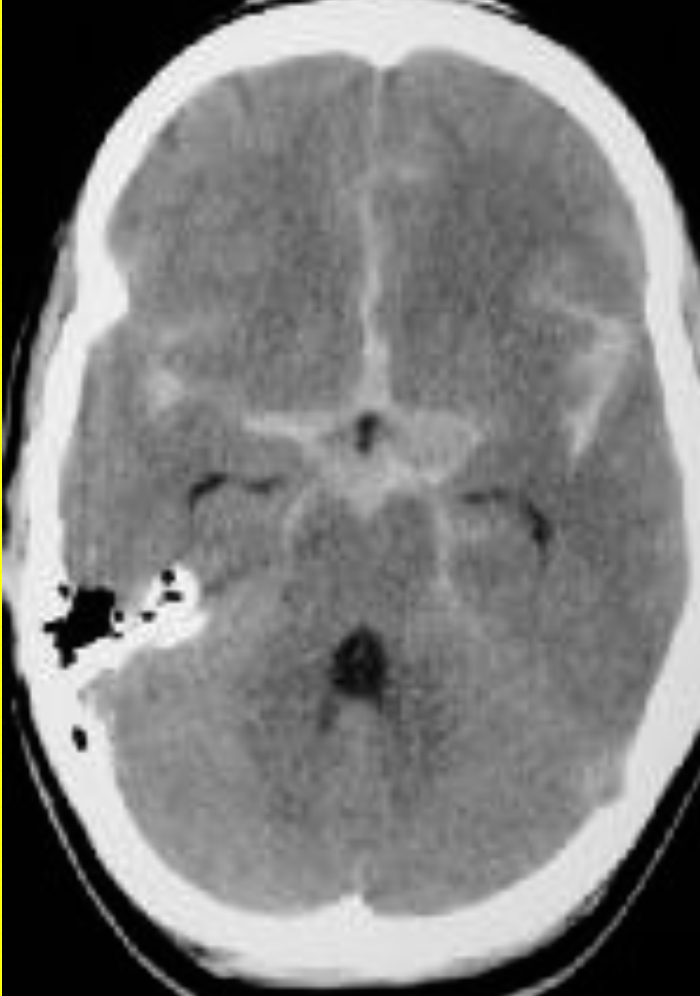

What’s ur finding ?

Star sign!!

Diagnosis?

Subarachnoid hemorrhage